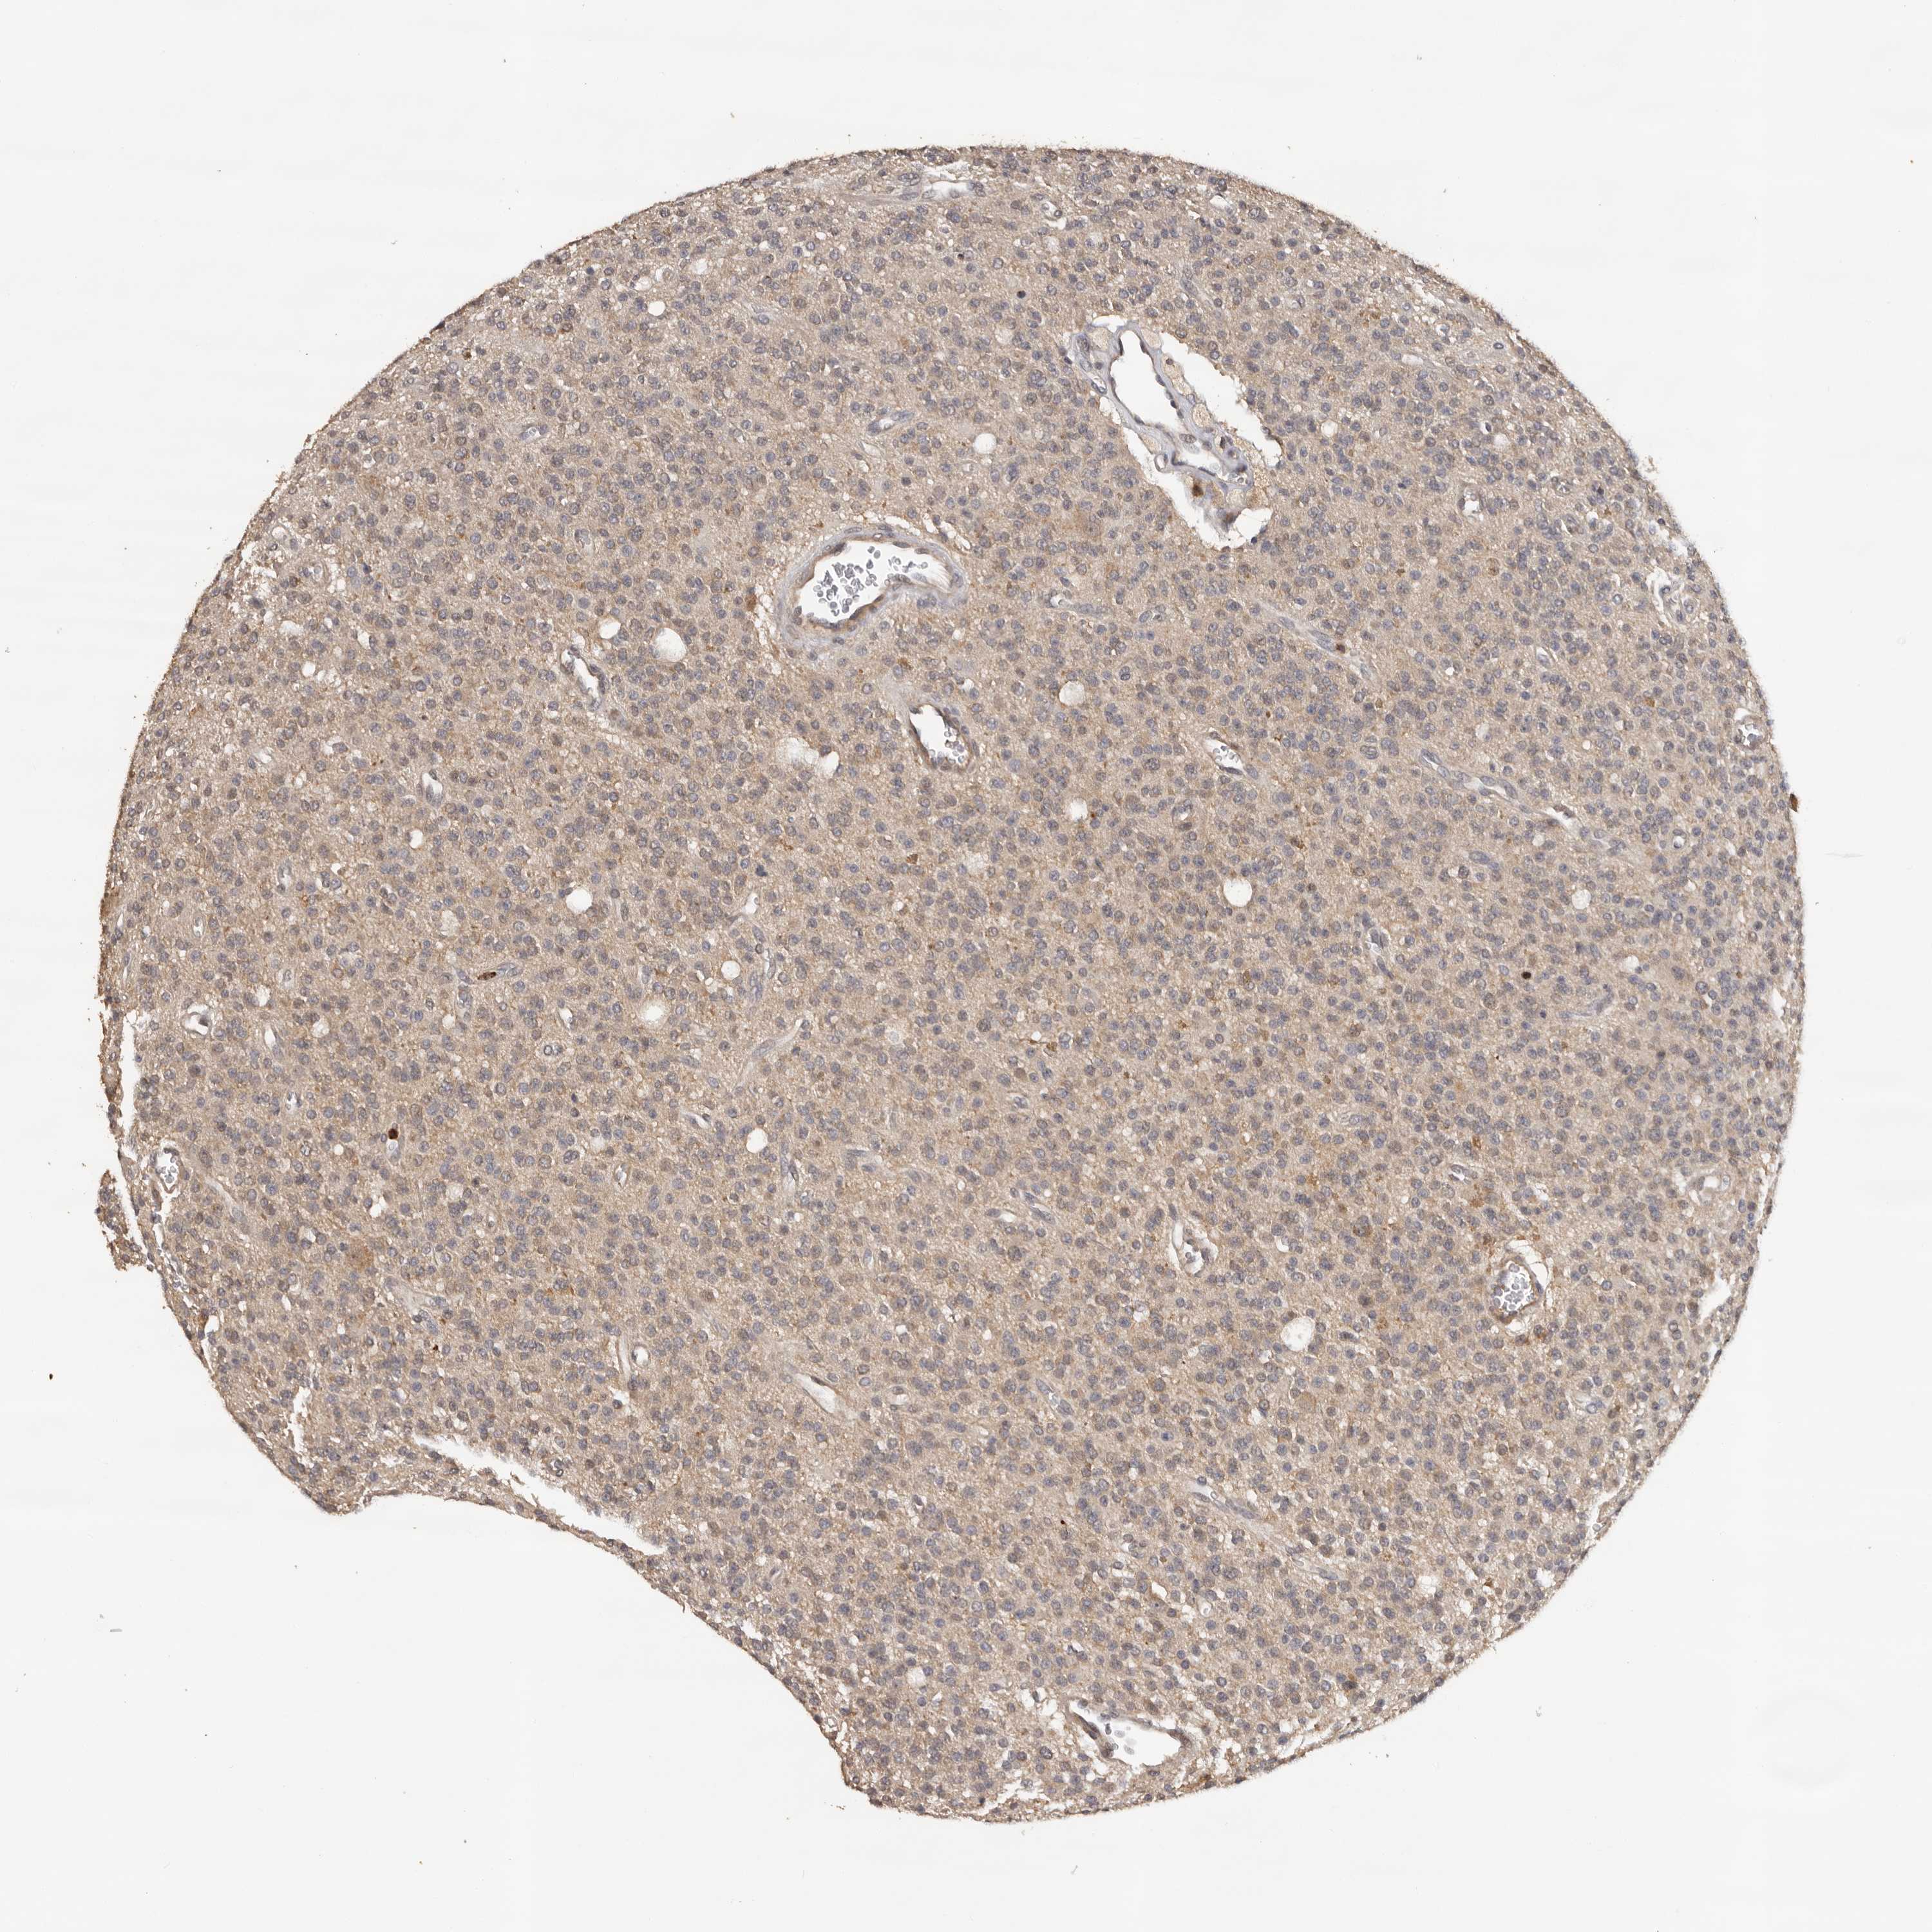

GLIOMA - Protein expressioni

A mouse-over function shows sample information and annotation data. Click on an image to view it in a full screen mode. Samples can be filtered based on level of antibody staining by selecting one or several of the following categories: high, medium, low and not detected. The assay and annotation is described here.

Note that samples used for immunohistochemistry by the Human Protein Atlas do not correspond to samples in the TCGA dataset.

Antibody stainingi

Antibody staining in the annotated cell types in the current human tissue is reported as not detected, low, medium, or high, based on conventional immunohistochemistry profiling in selected tissues. This score is based on the combination of the staining intensity and fraction of stained cells.

Each image is clickable and will lead to virtual microscopy that enables deeper exploration of all samples and also displays staining intensity scores, fraction scores and subcellular localization as well as patient and tissue information for each sample.

Antibody HPA023081

Antibody HPA023103

Antibody HPA024795

Glioma, malignant, High grade

Glioma, malignant, Low grade